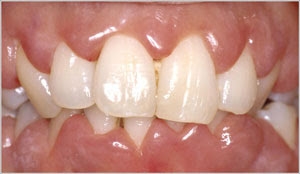

Enlargement of gums or gingiva is called gingival hyperplasia in the dental terms. This condition occurs due to abnormal multiplication of gingival tissue cells caused by various factors. Typical findings for gingival hyperplasia are swollen and enlarged gums. If you are suffering from gingivitis there will be gum bleeding as well as tenderness. The teeth get covered with the gums if the infection is too intense.  The patient is examined by a dentist and then the patient is sent for further examination if any further complications are seen.